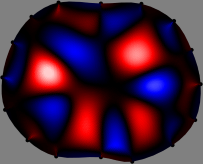

Figs. 3 and 4 compare the performance of the proposed FER method in (20) with the standard regularized least-squares method ((19) when is the identity matrix). The regularization parameter of the standard method was heuristically chosen for its best performance, and the parameter of the FER method was set to be one of three different values . The injection current was 1 mA at 100 kHz, and the frame rate was 9 frames per second. The reference frame at was obtained from the maximum expiration state. The measured data, , represent the voltage differences between each time and . The blue regions, which denote where conductivity decreased by inhaled air, increased during inspiration and decreased during expiration. The FER method with was clearly more robust than the standard method that produced more artifacts originated from the inversion process.

| Standard | |

||||||||||

| FER () | |

| FER () | |||||||||||